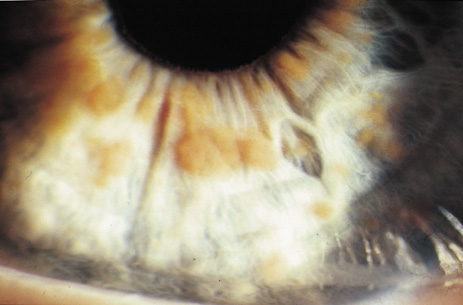

Lisch nodules are hamartomas (a tumor involving only those tissue elements normally found at the involved site) of the iris pigment epithelium. They are dome-shaped discrete lesions, are typically light brown in color, and may also be found in the angle.38 Lisch nodules appear earlier (33% at 2.5 years, 50% at 5 years of age)39 than neurofibromas. They are benign and can help to confirm diagnosis in children who may have café au lait spots as the only other clinical finding. Lisch nodules are present in nearly all adults with NF139,40 but are rare in NF2 (Fig. 3).41,42 Diffuse nodular iris nevi (also known as iris mamillations) should not be confused with Lisch nodules. Its clinical significance is not well established.43,44

Fig. 3. Neurofibromatosis type 1: Lisch nodules. These are hamartomas of the iris pigment epithelium. Lisch nodules are present in nearly all adults with NF1,39,40 but are rare in NF2.41,42